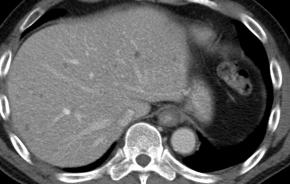

Comments Although the hepatic parenchyma may initially appear coarse, the liver actually shows numerous tiny hyperechoic foci with comet-tail artifacts scattered throughout the parenchyma. In addition, there are no accompanying findings suggestive of chronic liver disease or cirrhosis, such as liver contour blunting, surface nodularity, liver volume redistribution, dilatation of the portal vein, or splenomegaly.

• Multiple tiny low-attenuating lesions are scattered throughout the hepatic parenchyma, which is a characteristic CT finding of biliary hamartomatosis.